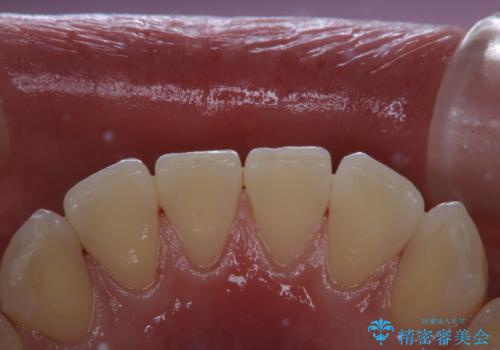

PMTC60分コース(保険外治療)を行いました。かなり久しぶりの歯科医院へ来院とのことで、プラーク(歯垢)・歯石・ステイン(着色)が付着していました。汚れを除去し、本来のご自身の歯質にすることでなにか異常があった際に発見しやすくなります。

PMTCで汚れを除去することは、虫歯や歯周病・口臭予防に効果的です。

お口の状態により間隔は個人差がありますが、PMTCは定期的に行うことが大切です。